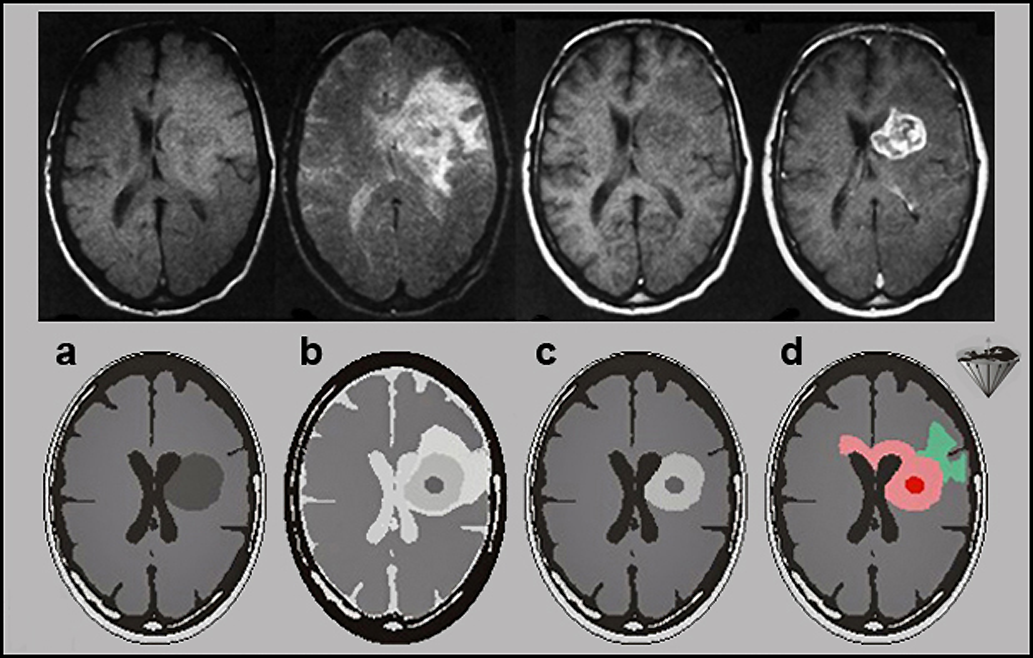

Figure 13-11 is an example of the ability of an intravenous Gd contrast agent to enhance brain tumors. The application of a contrast agent allows the de­li­ne­ation and definition of tumor extent — with certain limitations, as explained in the fi­gu­re.

Figuras 13-11:

Top row: Malignant brain tumor.

(a) proton-density-weighted image; (b) T2-weighted image; (c) T1-weighted precontrast image; (d) T1-weighted postcontrast image.

Although it is obvious that a large mass displaces the lateral ventricles, an exact delineation of the tumor is impossible on the first three images. Edema is well seen on the T2-weighted ima­ge, but the dark tumor areas are poorly delineated. Only after the contrast agent administration does the tumor become bright and its active parts are well visible.

Bottom row: Graphic explanation of corresponding histology. The contrast agent only en­han­ces ab­sence or breakdown of the blood-brain-barrier and high-vascularity lesions.

(a) and (b) T1- and T2-weighted precontrast images of a highly malignant tumor similar to the one seen in the top row; (c) the T1-weighted postcontrast image — corresponding to (d) in the top row; and (d) the actual microscopic tumor extension through the corpus callosum, which is not divulged by the MR images. The enhanced image shows only the tumor region, with the effect on the blood-brain barrier.